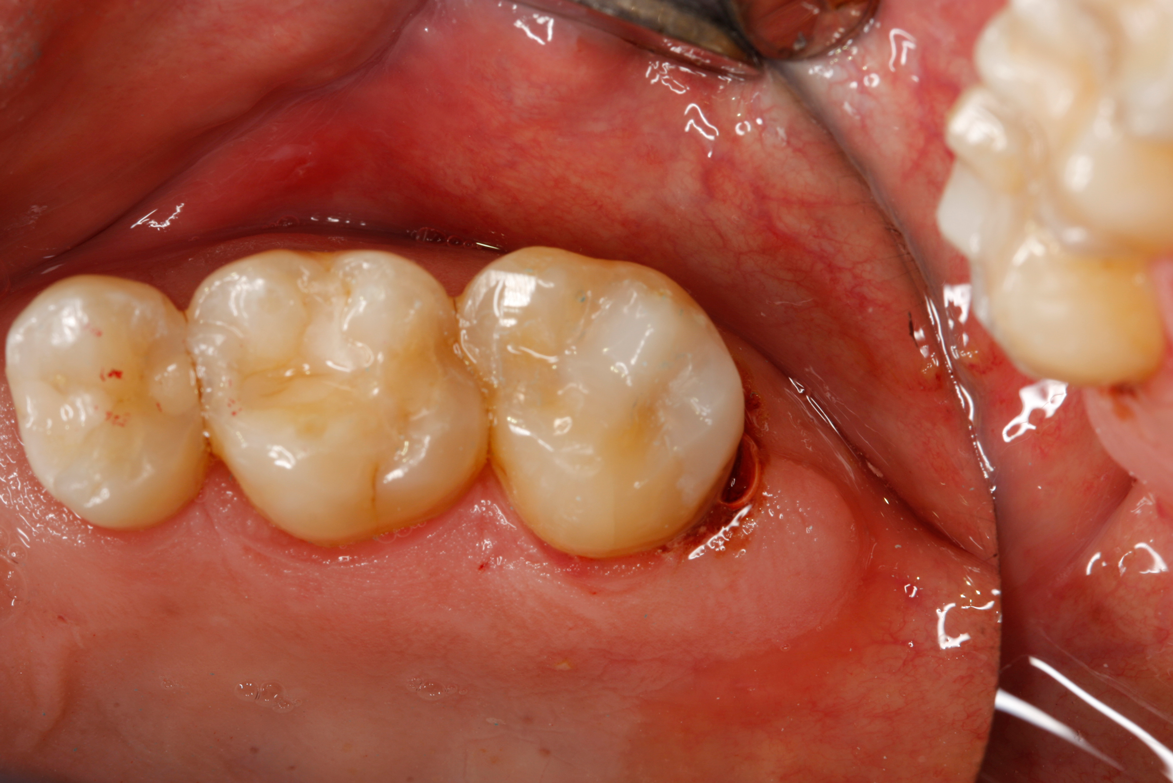

Fig 45. Finished restoration, ready for endodontic entry.

Figure 45

Fig 46. Close-up of polished surface.

Figure 46